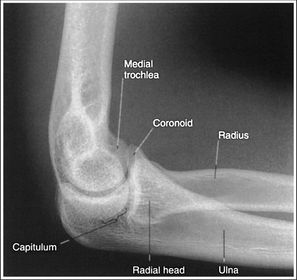

| Lateral Elbow | The elbow is elevated above the level of the shoulder radial head anterior to coronoid - should be superimposed capitulum too proximal to trochlea radial tuberosity seen - hand is pronated |

| Lateral Elbow | Elbow is depressed below the level of the shoulder radial head superimposed by coronoid capitulum too distal to medial trochlea |

| Lateral Elbow Evaluation Criteria | ANATOMY: distal humerus, proximal forearm, entire elbow joint CRITERIA: humeral epicondyles are superimposed radial tuberosity is invisible (if visible the hand is pronated) half of the radial head superimposed by coronoid process Elbow is flexed 90 degrees to see/not see fad pads 3 concentric arcs visible POSITIONING: CR perpendicular @ lateral epicondyle |